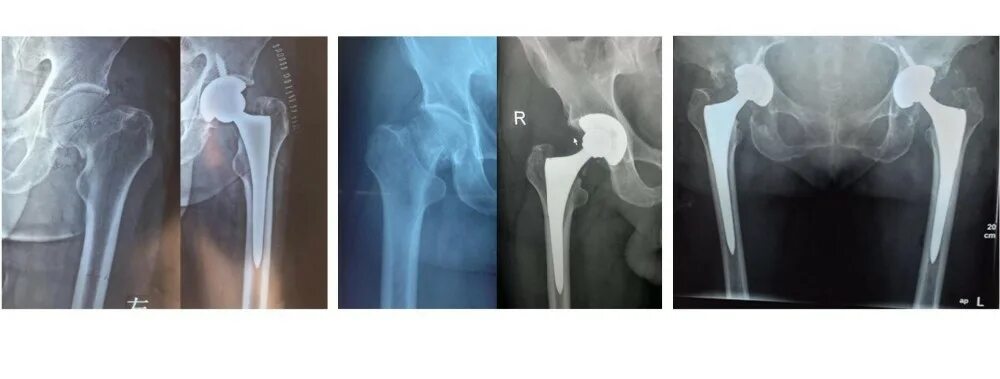

Причины эндопротезирования тазобедренного сустава